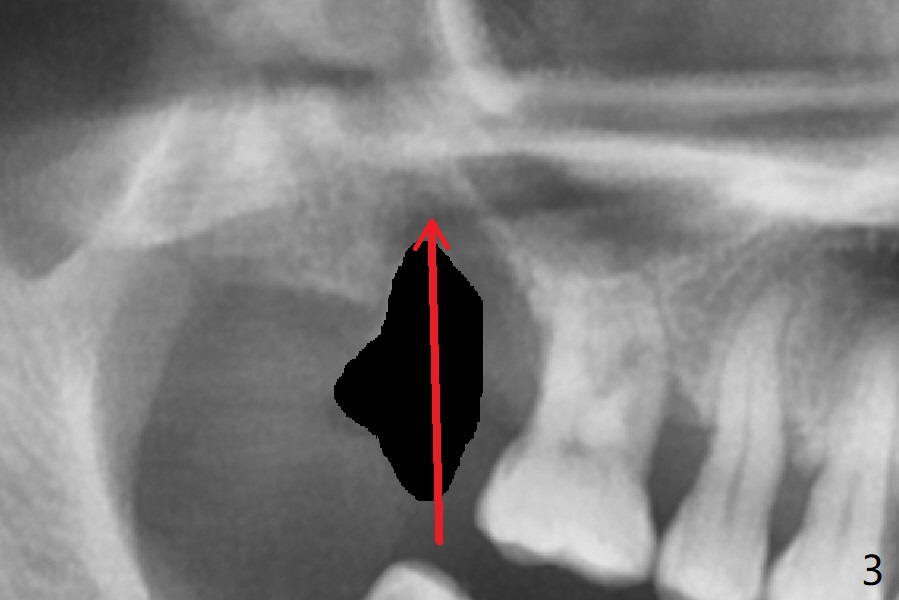

After extraction of the tooth #2 (Fig.1), osteotomy is supposed to be initiated in the mesial slope (Fig.2 arrow). With Magic Expanders (3-4.8 mm), osteotomy ends up in the bottom of the socket (Fig.3). Trajectory is found to be off when 4x9 and 5x9 mm dummy FC implants are placed with stability (Fig.4,5). The final implant, Magicore (5x7(3)mm, >29 Ncm), appears to be placed too deep for restoration (Fig.6,7); a screw retained crown may be a solution. PRF membrane and Vanilla (allograft) are used for sinus lift (no sinus membrane perforation). Following Vanilla graft in the socket gap (Fig.6 *), another piece of PRF membrane is used to cover socket opening. The membrane is fixed in place with suture and periodontal dressing. The implant seems to have osteointegrated 3.5 months postop (Fig.8). After change to 4.3x5 mm solid abutment and mesial surface adjustment, impression is taken for early loading because of removal of #14 implant. In fact the patient is satisfied with mastication improvement at #2 later on.